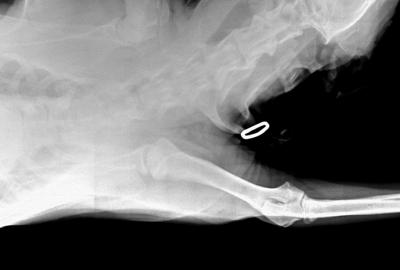

RTG Dysplazie loketního kloubu (DLK)